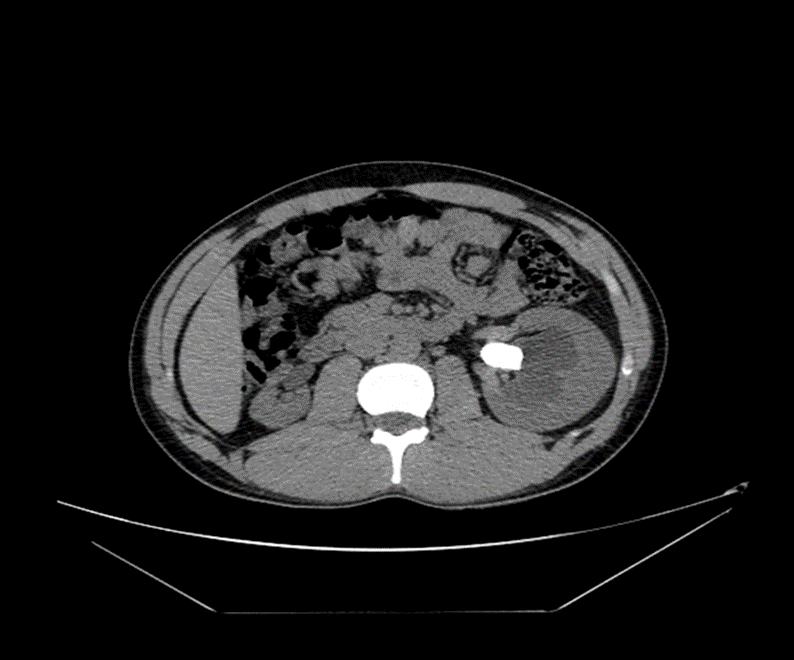

Diagnosis: CT show LT Renal stone

Renal stone on ultrasound